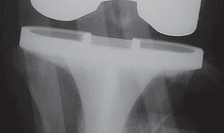

P ITFALLS As in revision total knee arthroplasty (TKA), the etiology of failure of the primary procedure must…